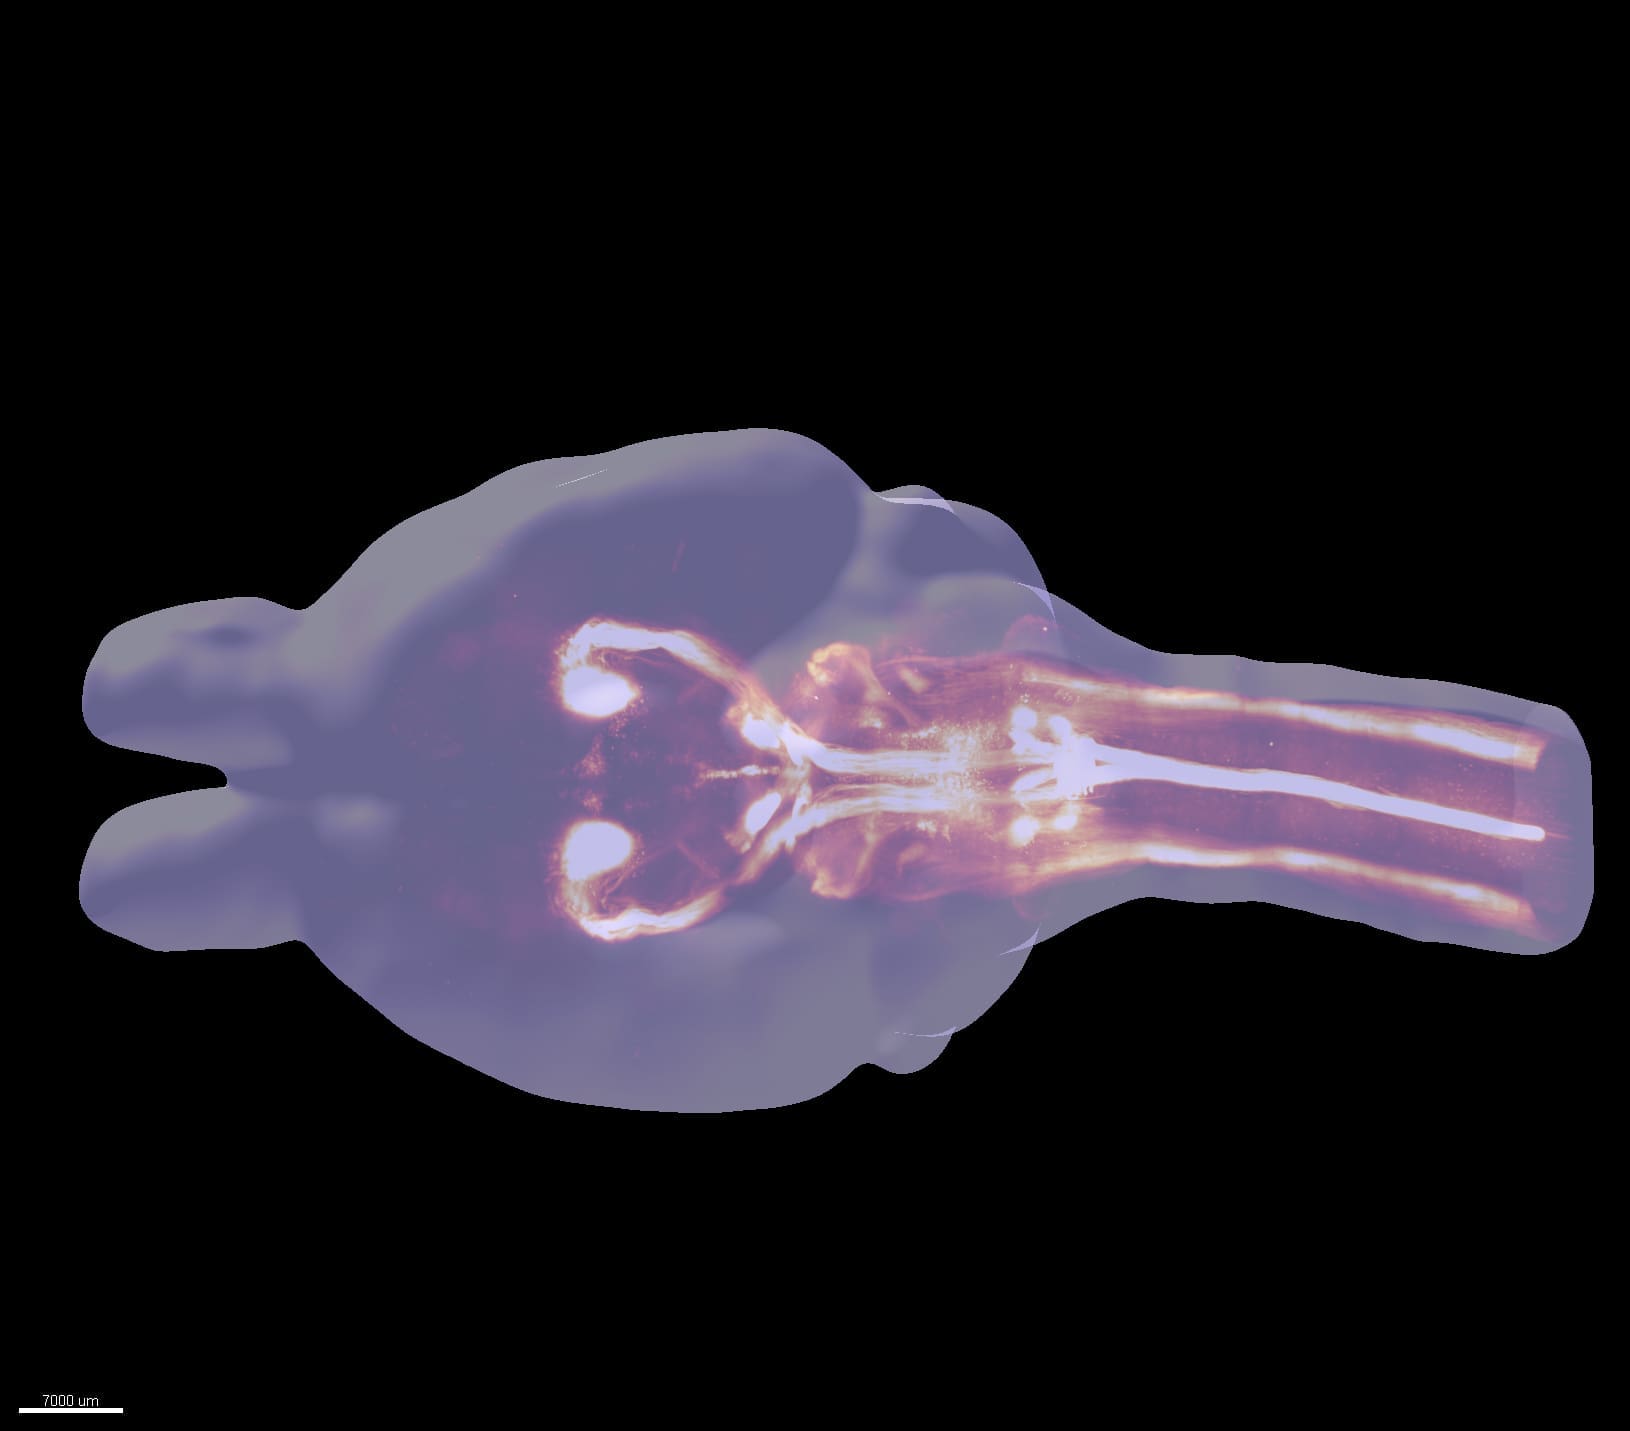

Revealing 3D anatomy with lightsheet microscopy

Developers around the world are pushing microscope technology to the extremes. Lightsheet microscopes image brain tissue down to individual neurons and offer unprecedented maps of nervous system structure and function.

Discovering new sub-cellular worlds in 3D brain samples

3D spatial transcriptomics may hold clues to future therapies for brain diseases. The technique measures gene expression from the RNA found in cells. It tells us what type of cell it is, exactly where it is, and can also indicate how a cell may interact with neighboring structures to the sides, above or below.